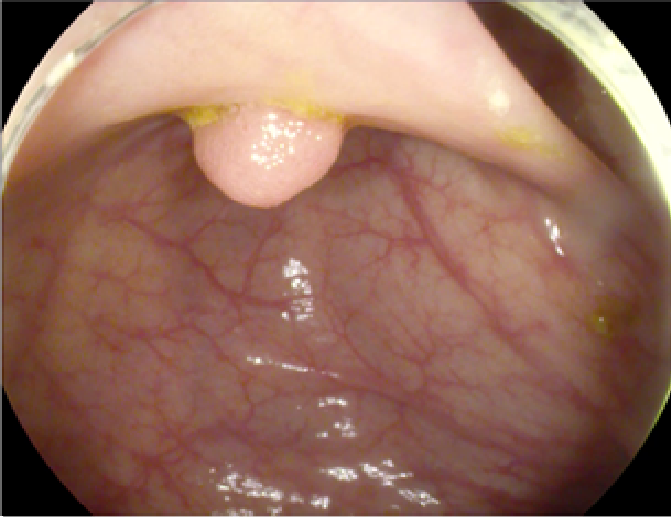

4.1 Dataset Specifications and Augmentation

The study used a publicly available dataset of polyp-frames obtained from the ETIS-Larib database [34], containing 196 polyp images. These images were obtained from 34 different colonoscopy videos of 44 different polyps with various appearances and sizes, having a resolution of 1225×96612259661225\times 966 pixels. The ground truth of polyp areas for polyp datasets is determined by expert video endoscopists. A CNN model trained with such a small amount of data is likely to be meaningless and unstable, so data augmentation was performed on the polyp dataset. Data augmentation had to be performed on the colonoscopy images by considering vivid variations. Otherwise over-fitting would have occurred. In a colonoscopy imagery, polyps exhibits large variations in location, color, and scale. Moreover, variations in brightness and definition also occur due varrying the view-point of the camera. Therefore, in addition to photometric distortions and geometric distortions, we also have considered zooming, shearing, and altering brightness as strategies for data augmentation.

For photometric distortions, we controlled brightness and contrast as an enhancement, while blurring by adding noise with a standard deviation (σ)𝜎(\sigma) of 1.0. Similarly, for geometric distortions, clock-wise rotation of the polyp images with angles of 90°90°, 180°180°, and 270°270° were performed. Zoom-in and zoom-out with zooming parameters such as 30.00% and 10.00% were performed to obtain different scales of polyp images. Lastly, shearing for both the x-axis and the y-axis was performed to shear the images from left to right and top to bottom, respectively. Fig. 4 shows photometric and geometric forms of image augmentation. In this way, we augmented the data set of the ETIS-Larib database from 196 polyp images to 2,156 images, which is more suitable for training the proposed deep CNN model.